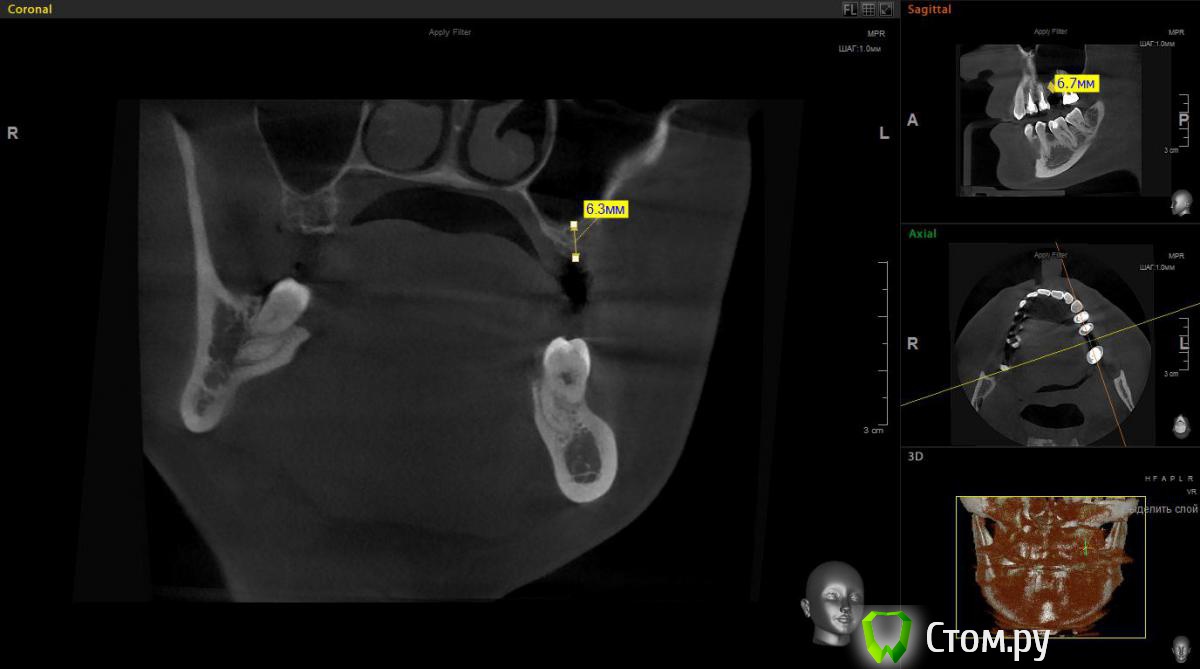

Евгений Ходыкин Опубликовано 1 ноября, 2014 Поделиться Опубликовано 1 ноября, 2014 Есть большое желание обойтись закрытым синусом в данной области. Ложе подготовить экспандерами, ими же поднять "дно". МР3 в пазуху (или чисто на сгустке оставить?). НРК по ситуации. Заранее спасибо за комменты Ссылка на комментарий

red_butler Опубликовано 1 ноября, 2014 Поделиться Опубликовано 1 ноября, 2014 Есть большое желание обойтись закрытым синусом в данной области. Ложе подготовить экспандерами, ими же поднять "дно". МР3 в пазуху (или чисто на сгустке оставить?). НРК по ситуации. Заранее спасибо за комменты мне кажется замеры сделаны не корректно, вы мерили от края гребня.реальная высота около 3 мм, соответственно делать нужно открытый Ссылка на комментарий

victor57 Опубликовано 1 ноября, 2014 Поделиться Опубликовано 1 ноября, 2014 Я считаю открытый делайте.гребень узкий,при формировании ложа импланта часть кости уйдет и,действительно,останется 3-4 мм Ссылка на комментарий

red_butler Опубликовано 1 ноября, 2014 Поделиться Опубликовано 1 ноября, 2014 (изменено) а откуда тогда нужно замерять, пардон?? там где ширина позволяет поставить винт, на вершине гребня ширина около 1.5 мм. поставьте в проге виртуальный имплант Изменено 1 ноября, 2014 пользователем red_butler Ссылка на комментарий

Чертков Александр Опубликовано 2 ноября, 2014 Поделиться Опубликовано 2 ноября, 2014 Жень, некорректно промерил...там 3-4 мм, я за открытый. Возможно сразу с винтом. По ситуации. Ссылка на комментарий